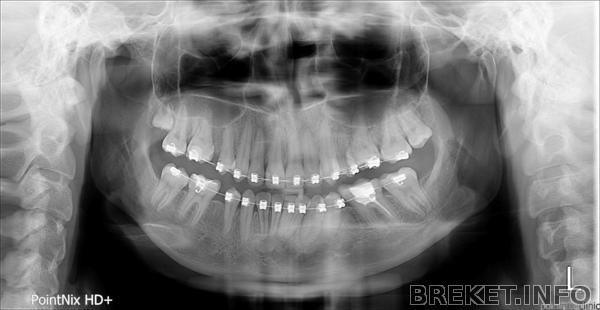

в итоге сделала снимок и я просто в шоке.

на снимке нижний шестой зуб справа.

lebedeva.e.b_p01_20150312_102520516.jpg

один канал просто не увидели. но подозреваю, что просто стало пох, т.к. лечила в бесплатной поликлинике. Читать далее »